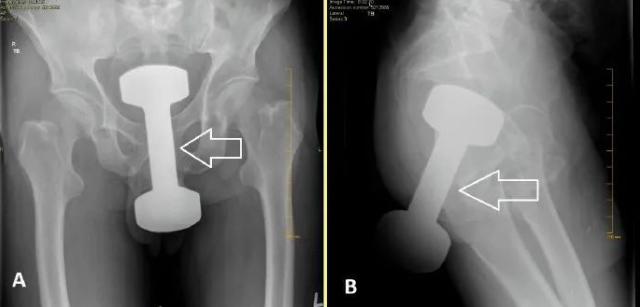

被塞进菊花的哑铃?